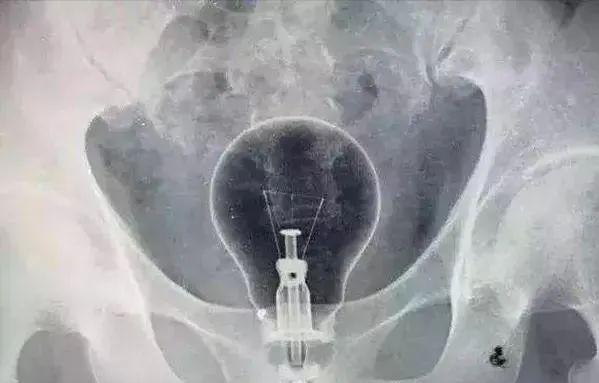

从外到里被撑开过度,可以是重度便秘的朋友用手指抠便便的时候太过*力暴**,或者有一些奇怪的东西被塞进了菊花里,导致菊花裂伤的情况。

(看!这个灯泡他真大!)